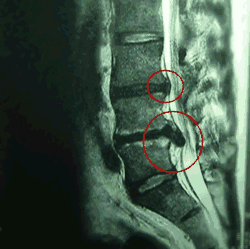

腰の骨ヘルニアのMRI側面画像

■赤丸印に飛び出した様子が見られます。

特に下は、ティアドロップ(涙のしずく)と言われています。